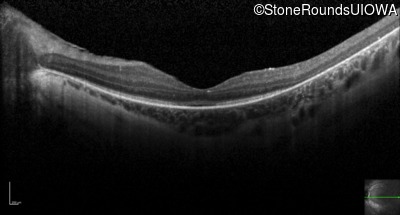

Optical Coherence Tomography - Right - 10/100 -1 sc

Exemplar / OCT Stack